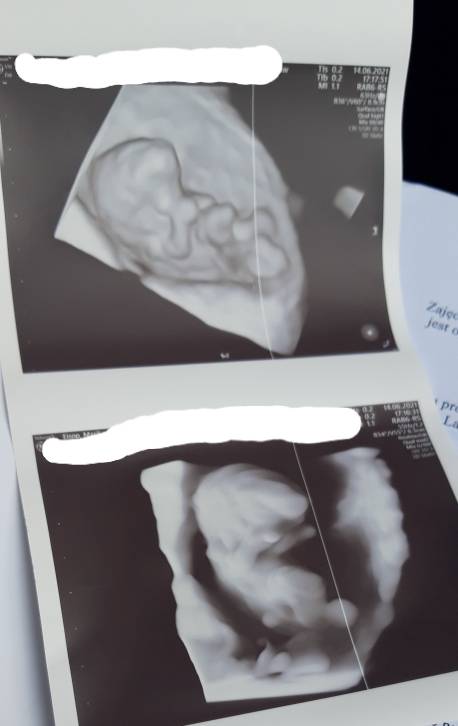

Dziewczyny, czy te wyniki są dobre?

IMG_20210614_183926.jpg